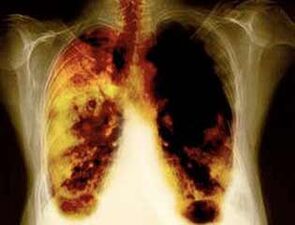

- Ridurre il rischio di sviluppare il cancro al polmone e molti altri tipi di cancro.

- Ridurre il rischio di sviluppare determinate malattie polmonari (ad esempio, malattia polmonare ostruttiva cronica).

- 10 anni dopo la cessazione del fumo del 40%, la probabilità di cancro ai polmoni diminuisce del 40%.